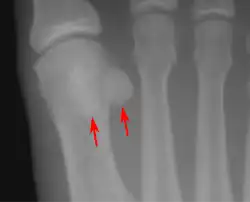

![]() Sesamoid bones at the distal end of the first metatarsal bone of the foot. | |

- In the foot—the first metatarsal bone usually has two sesamoid bones at its connection to the big toe (both within the tendon of flexor hallucis brevis).[9] One is found on the lateral side of the first metatarsal while the other is found on the medial side. In some people, only a single sesamoid is found on the first metatarsal bone.

Lateral view.[10]

Bipartite medial sesamoid bone under the first metatarsophalangeal joint of the great toe of the left foot of an adult woman.